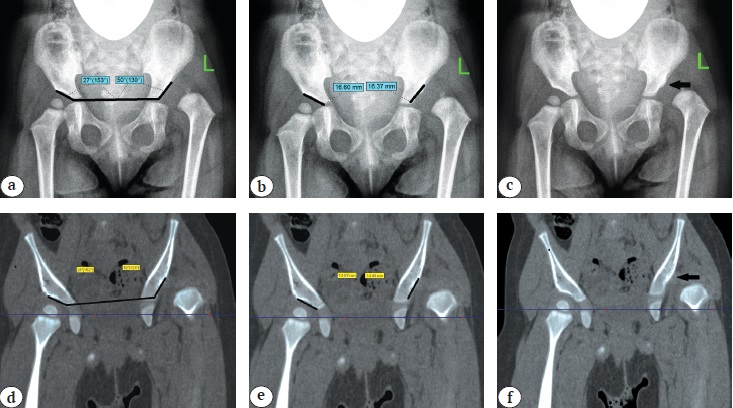

In order to objectify the data, the above-mentioned criteria were calculated using both X-rays and CT slice in the middle of the acetabulum (Figs. 1, 2).

Fig. 1. Determination in patients with Tönnis grade II DDH based on X-ray and CT results: a, d — acetabular index; b, e — extent of acetabulum arch (length of the sclerosis zone); c, f — presence of bone oriel (indicated by black arrow)